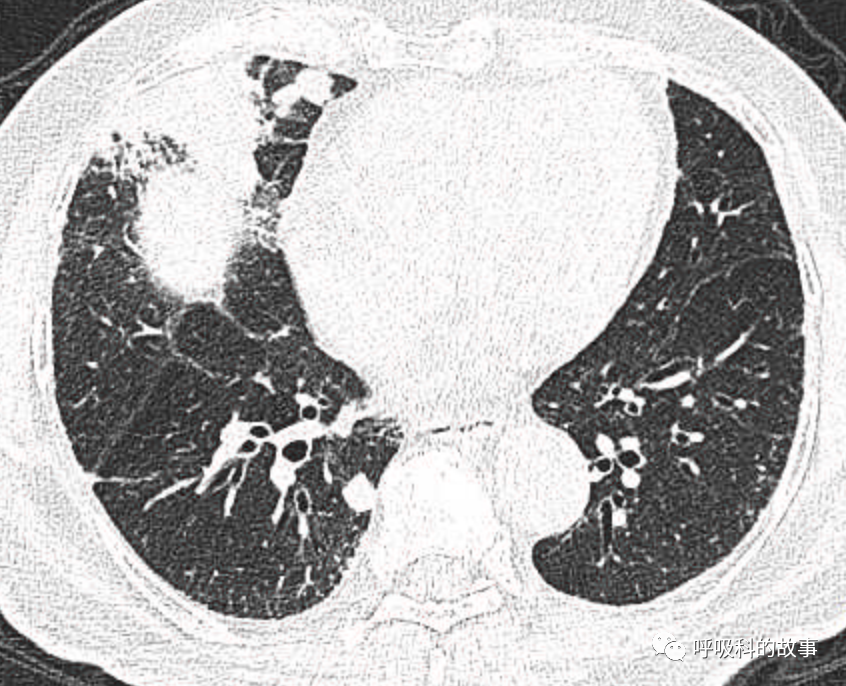

可是就在今年初,患者曾住在某院某科室,因为其他内科疾病住院。当时肺部CT也发现了在右中叶内侧段的高密度实变影,由于影像很类似肺炎,因此当成肺炎治疗。

图12-14:该患者各个角度的影像图像

(上下滑动查看全部图片)